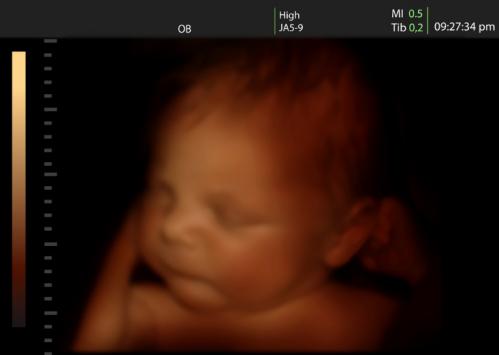

四维超声是这样的:

三维的基础上加上一个时间轴,也就是说这个立体图像能够随着时间进行变化

当遇到某些胎儿体表畸形时,三维、四维超声可能会提供一定的帮助,辅助超声医生诊断,也能让孕妇及家属更直观地看懂胎儿异常。

此时,三维超声成像往往比四维用得更多,因为三维图像作为一种静态成像对某一结构和病变显示的清晰度往往高于动态的图像。例如,胎儿唇裂。

而四维超声往往是为了动态观察某一结构的运动功能和变化情况。